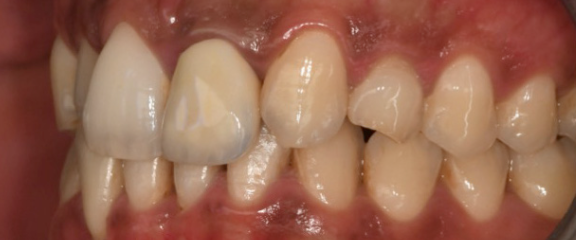

Digital impression captured with an intraoral scanner — buccal view Digital impression captured with an intraoral scanner — occlusal view

Step 1 Digital impressions captured with an intraoral scanner, providing the soft tissue and prosthetic reference data for the planning software.

Step 1 — Digital impression. An intraoral scan captured the soft tissue anatomy and the existing dentition. This provides the prosthetic reference — showing the software exactly where the final crown needs to sit.